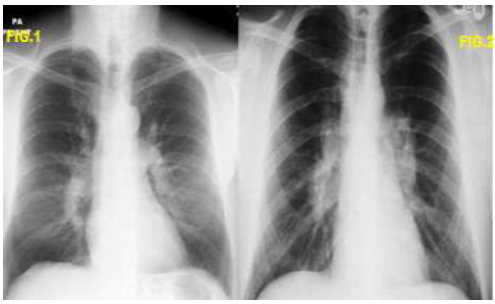

Analise as duas imagens abaixo e assinale a alternativa correta: